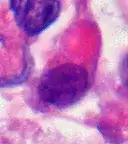

Immunohistochemistry

Immunohistochemistry for INI1, the product of the SMARCB1 gene typically defective in AT/RT: Note the loss of brown staining in the nuclei of tumor cells with defective SMARCB1 as compared to retained staining of nuclei of vascular cells (internal positive control).

Examination of the cerebrospinal fluid is important (CSF), as one-third of patients will have intracranial dissemination with involvement of the CSF. Large tumor cells, eccentricity of the nuclei, and prominent nucleoli are consistent findings.[29] Usually only a minority of AT/RT biopsies have rhabdoid cells, making diagnosis more difficult. Increasingly it is recommended that a genetic analysis be performed on the brain tumor, especially to find if a deletion in the INI1/hSNF5 gene is involved (appears to account for over 80% of the cases). The correct diagnosis of the tumor is critical to any protocol. Studies have shown that 8% to over 50% of AT/RT tumors are diagnosed incorrectly.